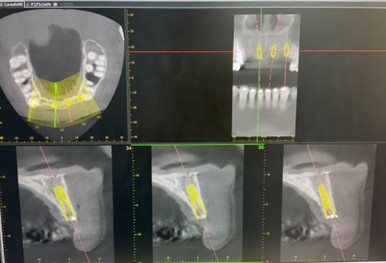

埋入シミュレーション

口腔内スキャナーで採得したデータとCT画像を融合させることで、インプラントの埋入位置・角度・深さを正確に誘導するマウスピース型の装置『サージカルガイド』を作製。

→口腔内スキャナーページへ

→サージカルガイドページへ

ガイドプロトコール